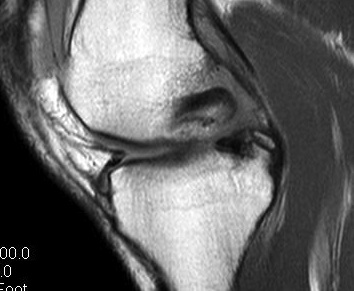

MRI

Advantage

- defines level of conus

- may need anterior rather than posterior surgery if lesion above conus